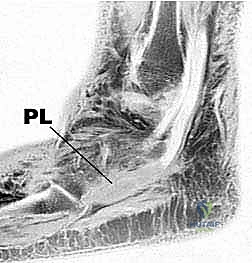

تتكون مجموعة أوتار الشظية من وترين رئيسيين ينشآن من عضلات في الجزء الجانبي (الخارجي) من الساق، وينزلان معًا خلف عظمة الكعب الخارجي:

- الوتر الشظوي القصير (Peroneus Brevis):

ينشأ هذا الوتر من العضلة التي تغطي الثلثين السفليين من عظم الشظية الجانبي في الساق. يتجه وتره إلى الأسفل والأمام، ليكون أعمق (أقرب للعظم) بالنسبة لوتر الشظية الطويل أثناء مرورهما خلف الكعب الجانبي (Lateral Malleolus). ينتهي هذا الوتر بالالتصاق بقوة في قاعدة مشط القدم الخامس (العظمة البارزة في منتصف الحافة الخارجية للقدم).

وظيفتة الأساسية: هي قلب الكاحل للخارج (Eversion)، مما يمنع القدم من الالتواء للداخل، بالإضافة إلى المساعدة في ثني الكاحل ظهريًا (Dorsiflexion). نظرًا لموقعه التشريحي المحصور، فهو الأكثر عرضة للتمزق الطولي الاحتكاكي. - الوتر الشظوي الطويل (Peroneus Longus):

ينشأ من منطقة أعلى في الساق، تحديدًا من رأس الشظية والثلثين العلويين من عظم الشظية الجانبي. يتجه وتره إلى الأسفل ليكون سطحيًا (فوق أو خلف) وتر الشظية القصير عند الكعب الجانبي. بعد تجاوزه الكعب، يغوص هذا الوتر تحت باطن القدم (الجانب الأخمصي)، ليعبر القدم قطريًا ويدخل في قاعدة مشط القدم الأول والعظم الإسفيني الأول في الجهة الداخلية للقدم.

وظيفته الأساسية: إنه قالب قوي للخارج (Evertor) ومثني أخمصي (Plantarflexor) لمشط القدم الأول. كما أنه يساهم بشكل حاسم في الحفاظ على القوس الطولي والعرضي للقدم أثناء مرحلة الدفع في المشي.